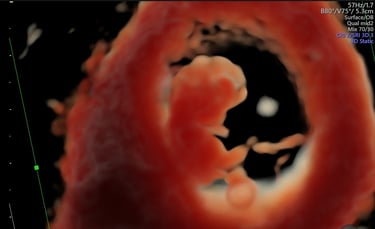

ecografía de viabilidad

4 - 11 semanas